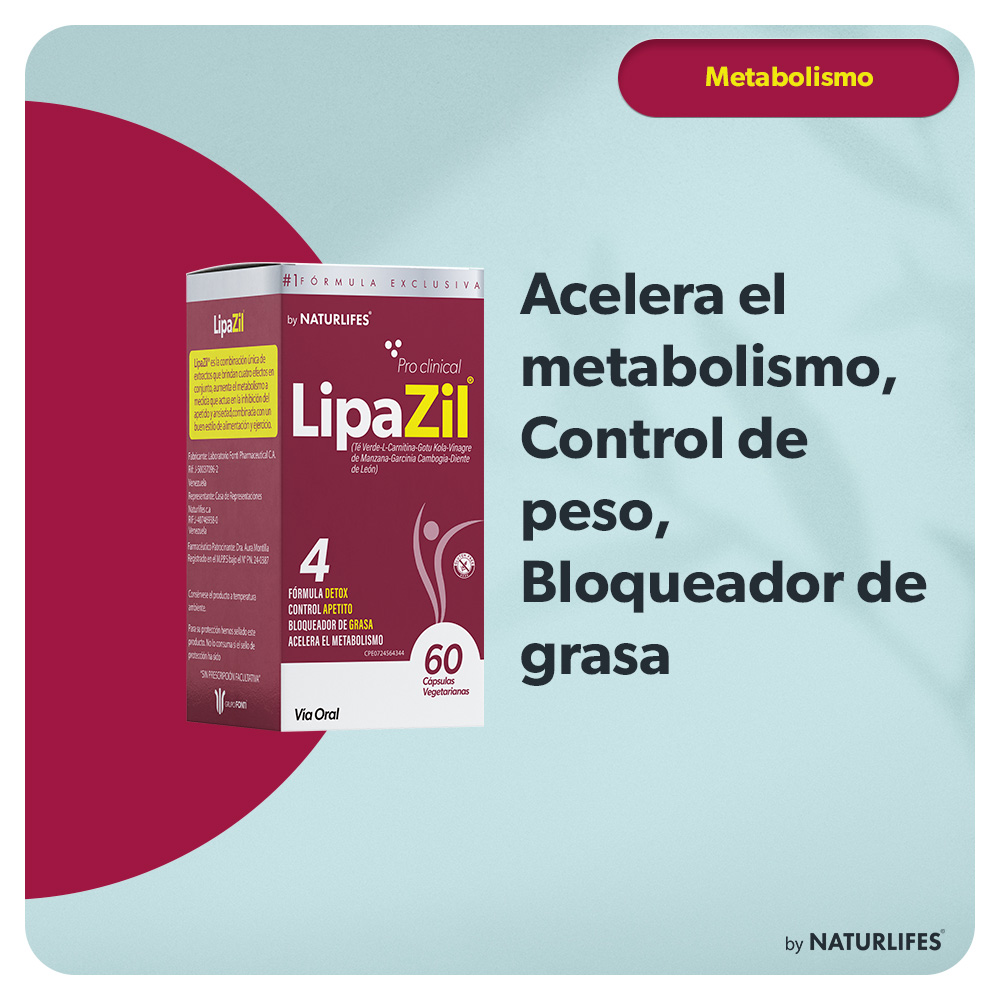

Lipazil®: Pierde Calorías más rápido

Lipazil®, es un fitofármaco innovador, que ha demostrado ser una herramienta efectiva en el manejo de la pérdida y control de peso. A través de una combinación única de extractos estandarizados, Lipazil ofrece una solución natural y segura para aquellos que buscan mejorar su salud y bienestar.

Tipo de Presentación

60 Cápsulas

Indicaciones Clínicas

Lipazil® es un Coadyuvante en:

- Tratamiento del control de peso

- Aceleración del metabolismo.

- Bloqueador de grasas con una fórmula de Detox..

Beneficios Clave de Lipazil®

Reducción de la masa grasa corporal

Mejora de la composición corporal

Disminución del riesgo de enfermedades cardiovasculares

Mejora de la función hepática y renal

Apoyo a la salud metabólica